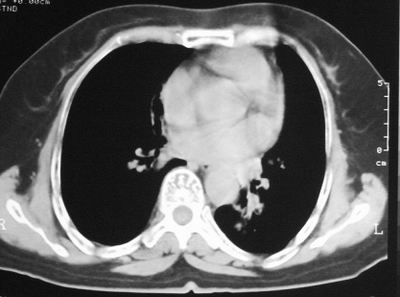

患者,女,64岁,4年前左腮腺"多形性"腺瘤手术治疗史.现复查胸部ct见左下肺块状影,该影与原左腮腺手术是否有联系?

本次复查胸部ct

左下肺软组织块影,有分叶、毛刺、空泡及胸膜牵拉征,左下肺周围性肺癌。

左肺下叶周围型肺癌,支持!(软组织肿块+分叶+毛刺+空泡+胸膜凹陷征)

左下肺后基底段实性肿块,周围有毛刺,病变周围有肺气肿,与降主动脉间有条带状影相连,病灶4年前查体发现,纵隔内未见肿大淋巴结。考虑.肺隔离症,建议增强扫描与周围型肺癌鉴别。